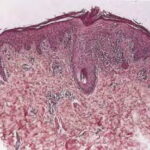

HISTOPATHOLOGY As with the morphology of the clinical lesions, pityriasis lichenoides can exhibit a range of histopathologic features encompassing acute, chronic, and intermediate lesional variants . All cases of pityriasis lichenoides contain an interface dermatitis that is denser and more wedge shaped in the acute lesions. The infiltrate is composed mainly of lymphocytes with a variable admixture of neutrophils and histiocytes. There is exocytosis, parakeratosis, and extravasation of erythrocytes. Epidermal damage ranges from intercellular and extracellular edema in less severe cases to extensive keratinocyte necrosis, vesicles, pustules, and ulcers. The acute variants can exhibit lymphocytic vasculitis with fibrinoid degeneration of blood vessel walls. Occasional CD30+ lymphoid cells and occasional atypical lymphoid cells may be seen as a non-specific finding in many cutaneous lymphoid infiltrates. The presence of an appreciable numbers of these cells is not consistent with classic pityriasis lichenoides of any type and should raise concern for the lymphomatoid papulosis-CD30+ anaplastic large cell lymphoma disease spectrum.74 Other immunohistologic features and the clonality of pityriasis lichenoides are discussed in Etiology and Pathogenesis. Differential Diagnosis The differential diagnosis of pityriasis lichenoides includes many papular eruptions . Those that develop crusts, vesicles, pustules, or ulcers are grouped with PLEVA, whereas those that form predominantly scaly papules are grouped with PLC. Most of them can be excluded based on history and typical clinicopathologic features. A few, such as secondary syphilis and viral-associated lesions, also can be excluded based on serologic tests. Among the most challenging diseases to distinguish from pityriasis lichenoides are lymphomatoid papulosis and macular or papular variants of MF. As detailed earlier, the presence of large atypical lymphoid cells (often CD30+) differentiates lymphomatoid papulosis from pityriasis lichenoides.Macular or papular variants of MF are rare. They exhibit classic features of MF, including small atypical epidermotropic lymphoid cells with convoluted nuclei and a band-like superficial dermal lymphoid infiltrate. Complications Secondary infection is the most common complication of pityriasis lichenoides. PLEVA may be associated with low-grade fever, malaise, headache, and arthralgia. Patients with PLUH can develop high fever, malaise, myalgia, arthralgia, and gastrointestinal and central nervous system symptoms. Occasionally, debilitated patients may die. PLC has been associated uncommonly with LPP in children. Despite